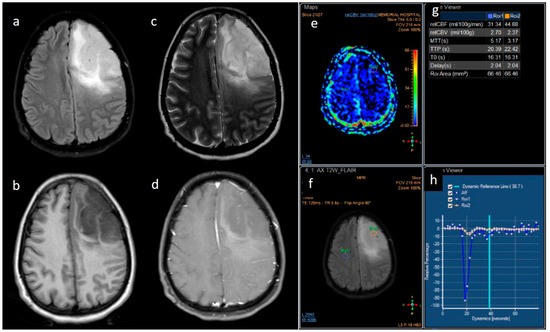

3.2. MRI Parameters of IDH-Wildtype vs. Mutant Phenotype Tumors

| Variable | Parameter | IDH-Mutated (n = 19) | IDH-Wildtype (n = 129) | p-Value |

|---|---|---|---|---|

| Enhancement I | Mild | 9 (47.4) | 5 (3.9) | <0.001 |

| Moderate | 6 (31.6) | 25 (19.4) | ||

| Severe | 4 (21.1) | 99 (76.7) | ||

| Enhancement III | Rim | 6 (31.6) | 104 (80.6) | <0.001 |

| Nodular | 0 | 2 (1.6) | ||

| Patchy | 11 (57.9) | 13 (10.1) | ||

| Solid | 2 (10.5) | 10 (7.8) | ||

| Necrosis | None | 3 (15.8) | 3 (2.3) | <0.001 |

| <25% | 11 (57.9) | 14 (10.9) | ||

| 25- 50% | 2 (10.5) | 35 (27.1) | ||

| >50% | 3 (15.8) | 77 (59.7) | ||

| Dural enhancement | AbsentPresent | 07 (70.0) | 31 (24.0)48 (52.7) | 0.013 |

| Edema | None | 3 (15.8) | 3 (2.3) | 0.025 |

| <tumor volume | 11 (57.9) | 68 (52.7) | ||

| Equal to tumor volume | 4 (21.1) | 35 (27.1) | ||

| >tumor volume | 1 (5.3) | 23 (17.8) | ||

| Cysts * | No | 11 (57.9) | 115 (89.1) | 0.001 |

| Yes | 6 (31.6) | 14 (10.9) | ||

| Subcortical involvement | Involved | 18 (94.7) | 94 (72.9) | 0.044 |

| Not involved | 1 (5.3) | 35 (27.1) | ||

| rCBV | Median (IQR) | 1.8 [1.4–2.0] | 2.6 [1.9–3.5] | 0.001 |